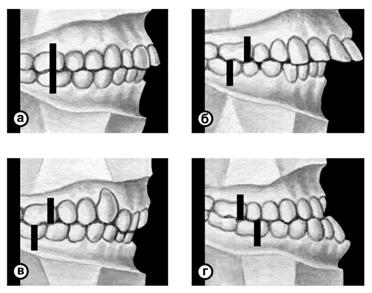

Рис. 5а). Схематическое изображение челюстей при основных разновидностях нормального прикуса (вид сбоку): ортогнатический прикус.

Рис. 5б). Схематическое изображение челюстей при основных разновидностях нормального прикуса (вид сбоку): прогенический прикус.

Рис. 5в). Схематическое изображение челюстей при основных разновидностях нормального прикуса (вид сбоку): прямой прикус.

Рис. 5г). Схематическое изображение челюстей при основных разновидностях нормального прикуса (вид сбоку): бипрогнатический прикус.